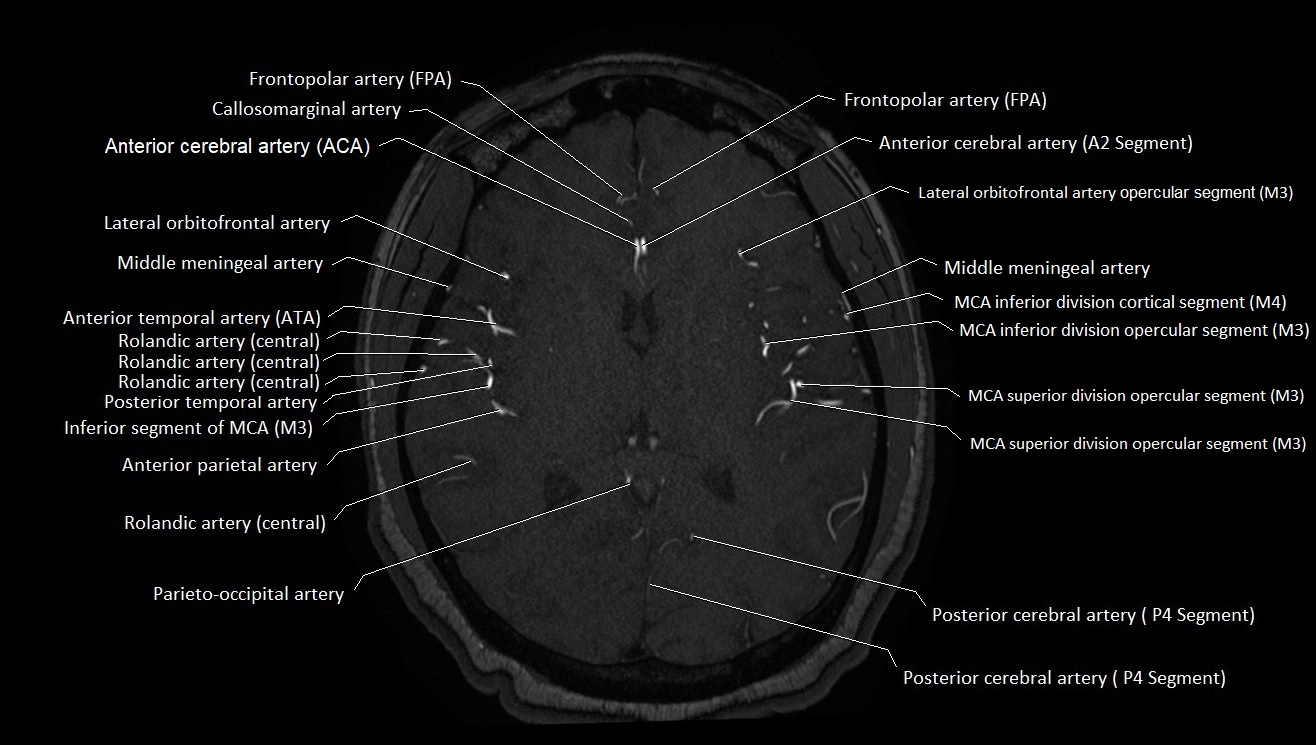

MRI images

image